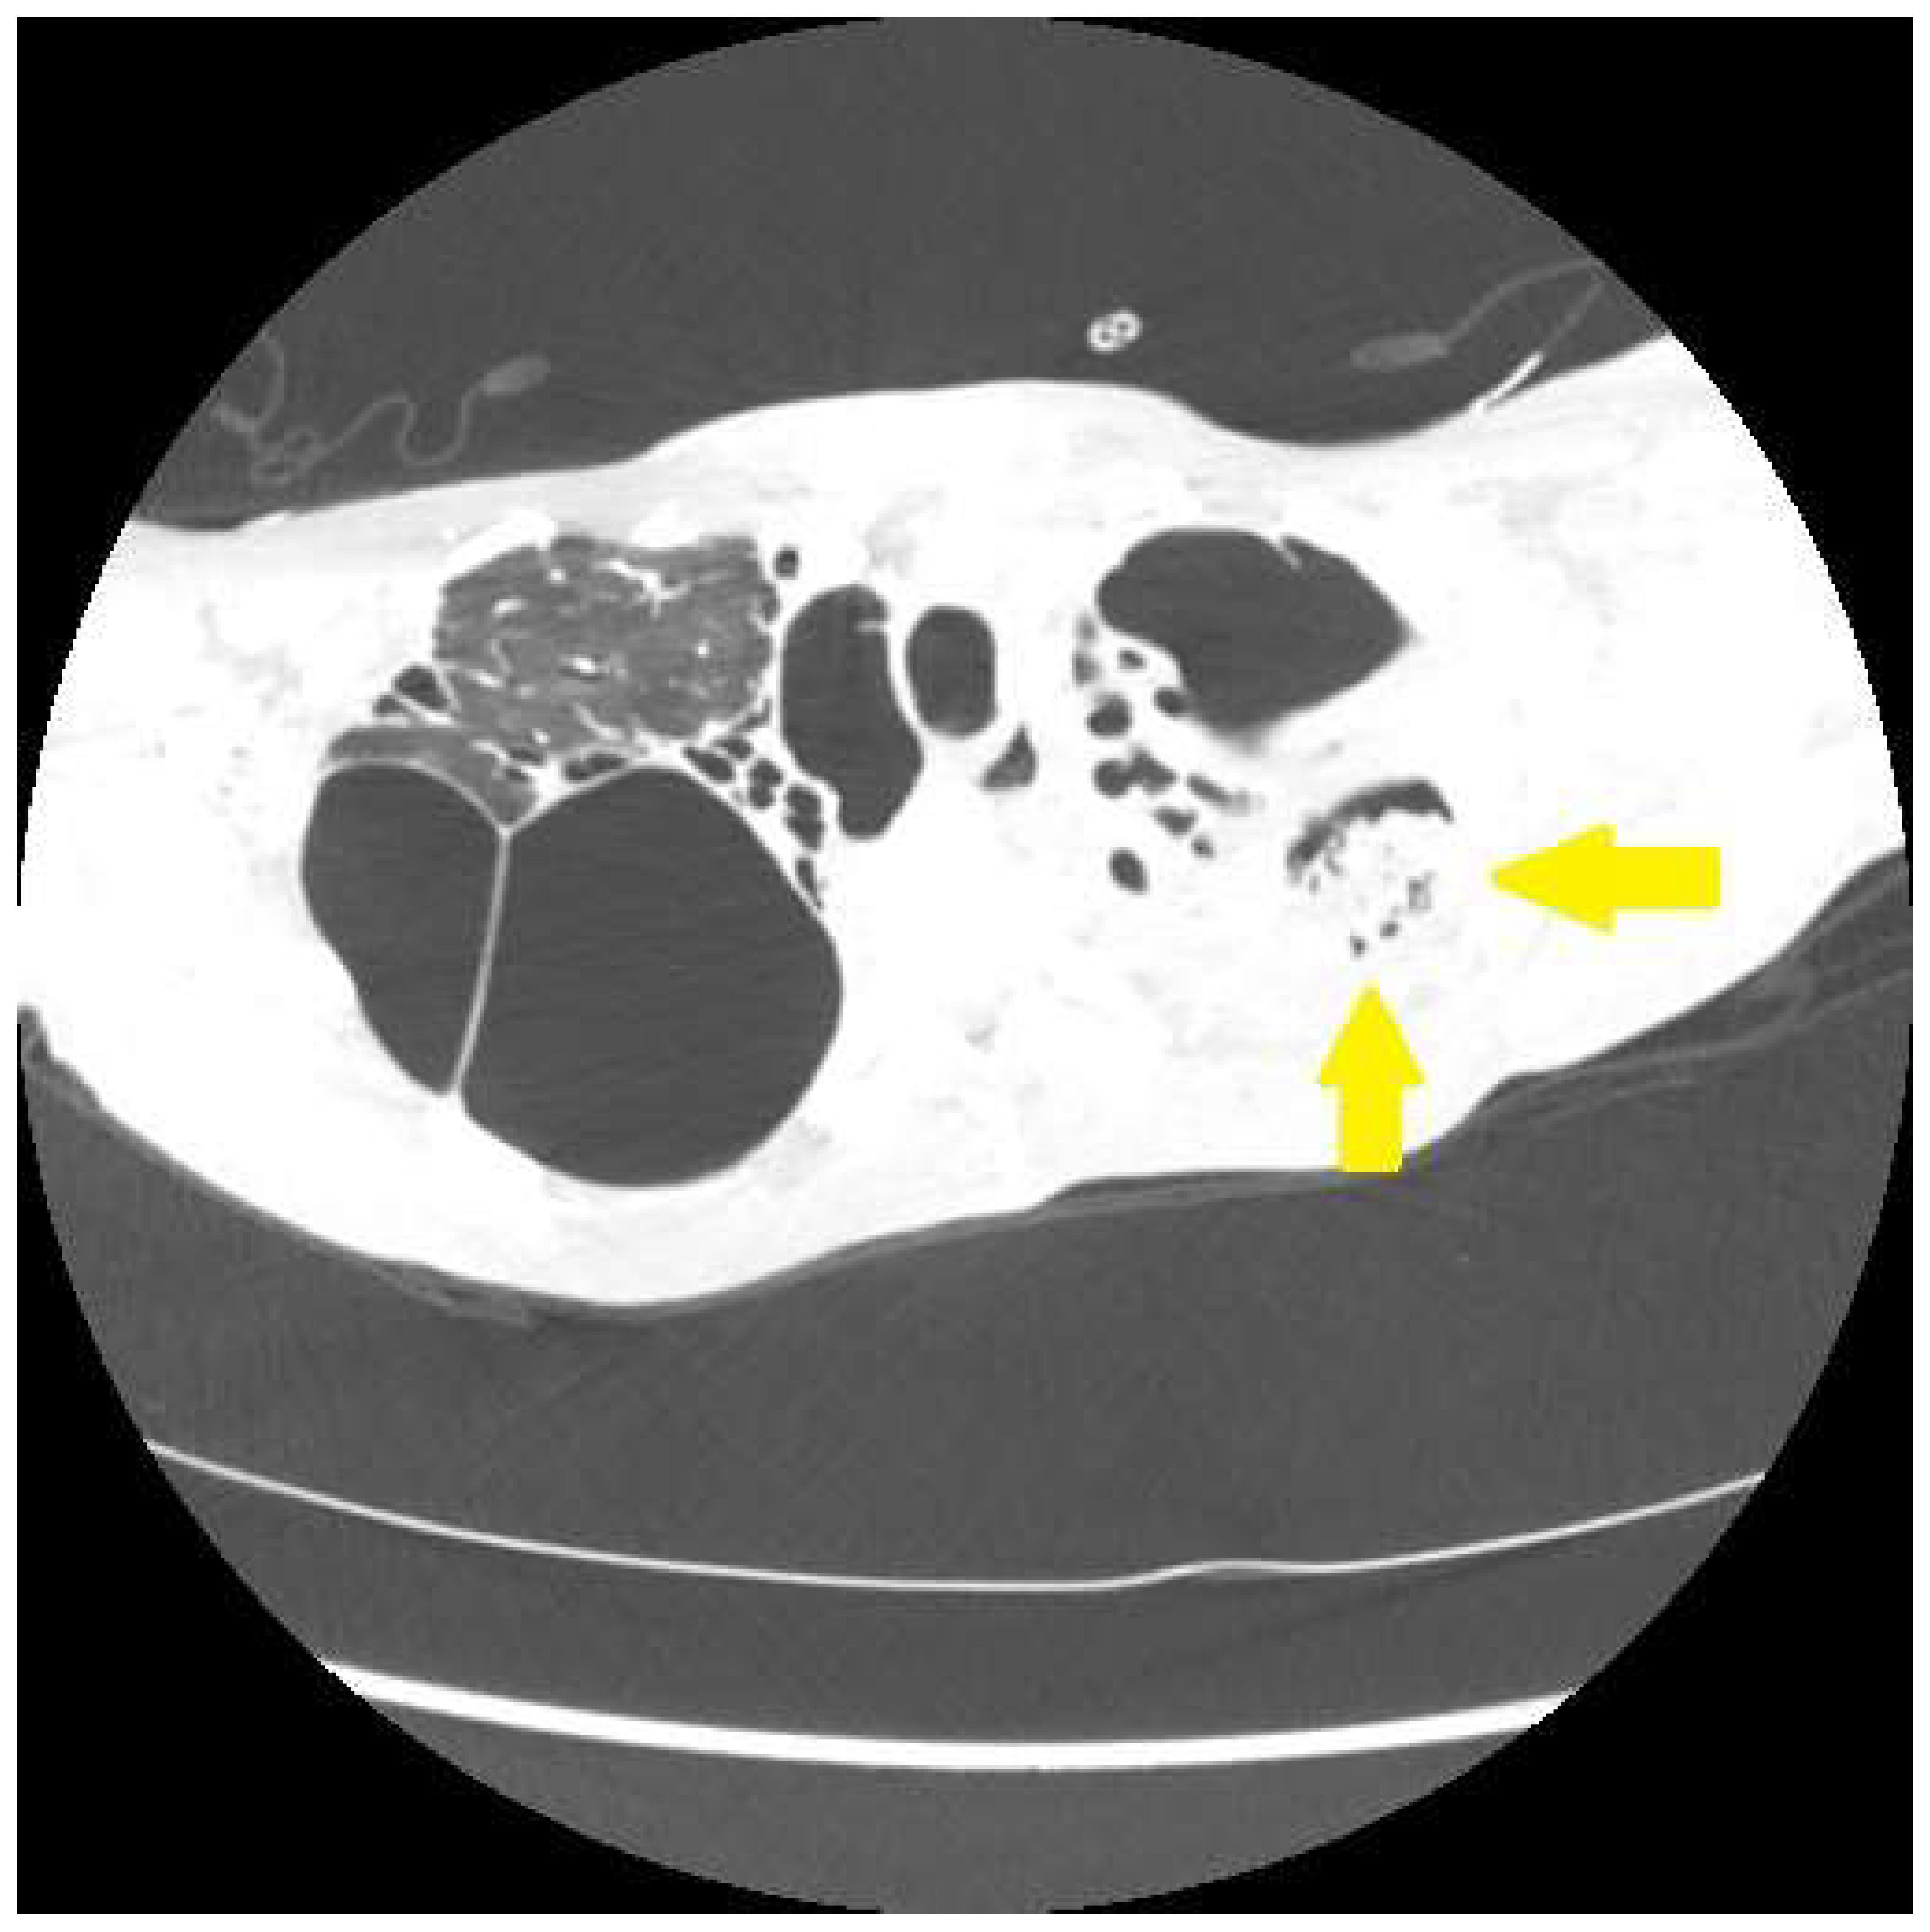

| Bronchiectasis | Fibrocystic sarcoidosis | Bronchiectasis from airway fibrosis from previous granulomatous inflammation. Hemoptysis from infectious bronchitis/bronchiectasis |

| Aspergilloma/Chronic aspergillus lung infection | Fibrocystic sarcoidosis | Aspergillus colonization of devitalized lung with subsequent locally invasive disease |

| Pulmonary hypertension | Many forms of sarcoidosis, most commonly fibrocystic disease | Pulmonary hypertension leads to vascular engorgement and a hemorrhagic diathesis that may be exacerbated by infection, granulomatous inflammation |